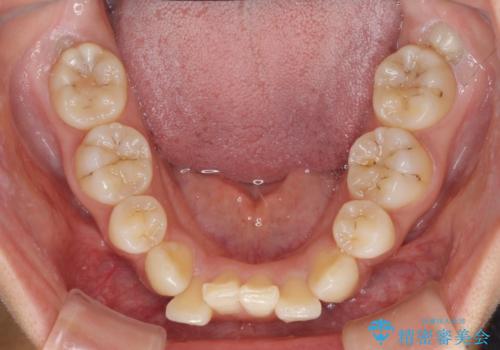

- 以前の矯正治療の後戻りにより、上下の前歯がでこぼこになってしまったことを気にして来院された患者様です。

口元がこれ以上突出することなく前歯の叢生が改善できるよう、歯と歯の間を削ってスペースを獲得し、インビザラインを用いて整えていくこととしました。

目安の装着時間である1日22時間をしっかりと実践してくださり、半年強という短期間で治療を終えることができました。